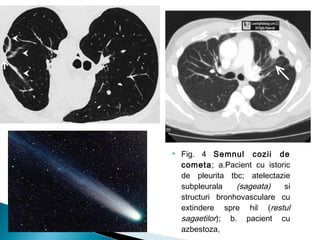

 Fig. 4 Semnul cozii de

cometa; a.Pacient cu istoric

de pleurita tbc; atelectazie

subpleurala (sageata) si

structuri bronhovasculare cu

extindere spre hil (restul

sagaetilor); b. pacient cu

azbestoza,